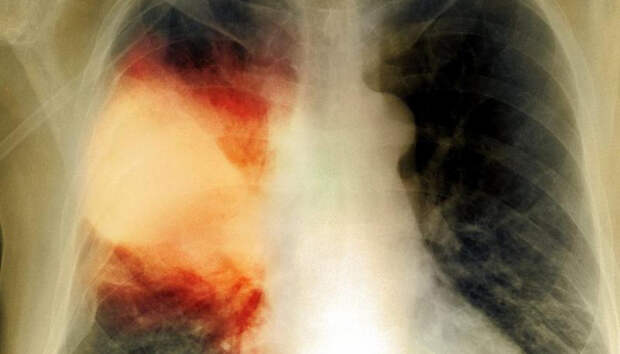

За минувшие сутки с воспалением легких в республике госпитализировано девять человек Девять человек за сутки госпитализированы с внебольничной пневмонией в Карелии, сообщает оперштаб по борьбе с распространением коронавирусной инфекции. Летальных исходов не зарегистрировано. Начиная с 1 апреля, с внебольничной пневмонией госпитализированы 1337 пациентов, 78 человек умерли (с учетом пациентов, госпитализированных ранее указанного периода).